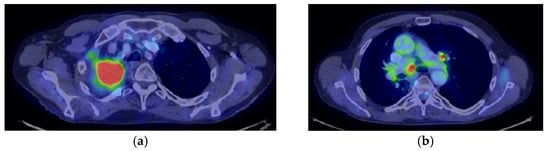

His current treatment was Eliquis 2.5 mg, one tablet two times a day; Betaloc 50 mg, ½ tablet in the morning; Prestarium 5 mg, ½ tablet in the evening; Rosuvastatin 10 mg, one tablet in the morning; Aspenter 75 mg, one tablet/day; Euthyrox 50 mg, one tablet/day; Urorec 8 mg and one tablet/day. The staging imaging (PET-CT) from 2017 revealed the following images (as shown in Figure 1a–e):

Figure 1.

PET CT. (a) T—spiculiform LSD tumor formation of 44 × 57 × 63 mm with SUV = 12.59, with central necrosis; (b) the tumor invades the superior apical and mediastinal pleura; (c) N—metabolically active mediastinal ADP with SUV max = 7.43 located in the Ao-pulmonary window (14 × 9 mm), (d) infracarinal (12.8 mm) and bilateral hilar (right maximum 21 × 16 mm and left maximum 11 × 7 mm); (e) M—metabolically active focus with SUV = 5.6 right humeral head, which corresponds to a small interruption of the bone cortex.

Reevaluation of PET CT 06/03/2018 vs. PET CT from 07/2017 highlighted stable disease (primary tumor regression by 12.87%: 29 × 59 mm vs. 44/57/63 and metabolic: SUV = 7.89 vs. 12.59) and metabolic progression on bilateral mediastinal and hilar lymph nodes: SUV 8.8 vs. 7.43) and M1OSS (right humeral head): SUV 6.04 vs. 5.6) (Figure 2a–e).

(a–e) PET CT reevaluation.